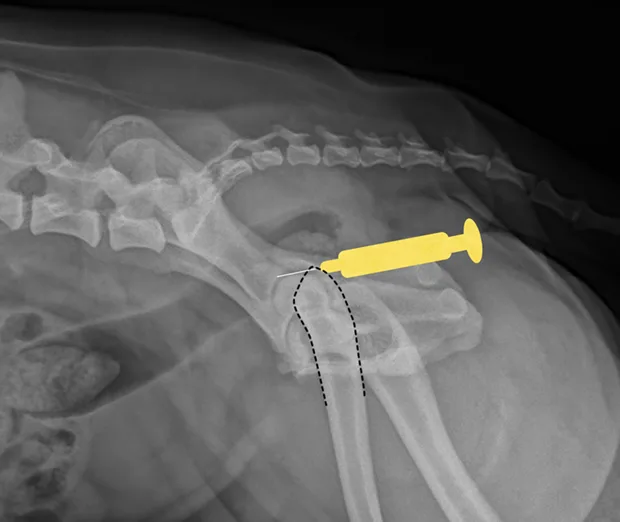

Shoulder

Place the patient in lateral recumbency with the shoulder joint in a neutral position. For large dogs, insert the needle about 0.5–1 cm distal to the acromion process of the scapula in a lateral-to-medial direction; a lateral radiograph of the shoulder joint may help determine the distance from the distal acromion to the joint space. The needle may need to be passed in a slightly dorsal direction to enter the joint. A 1.5-inch needle is adequate for even large-breed dogs.

Craniocaudal view of shoulder. Place needle just distal to the acromion (yellow dot), angled slightly dorsally.

Lateral view of shoulder. Insert needle just distal to the acromion (yellow dot).